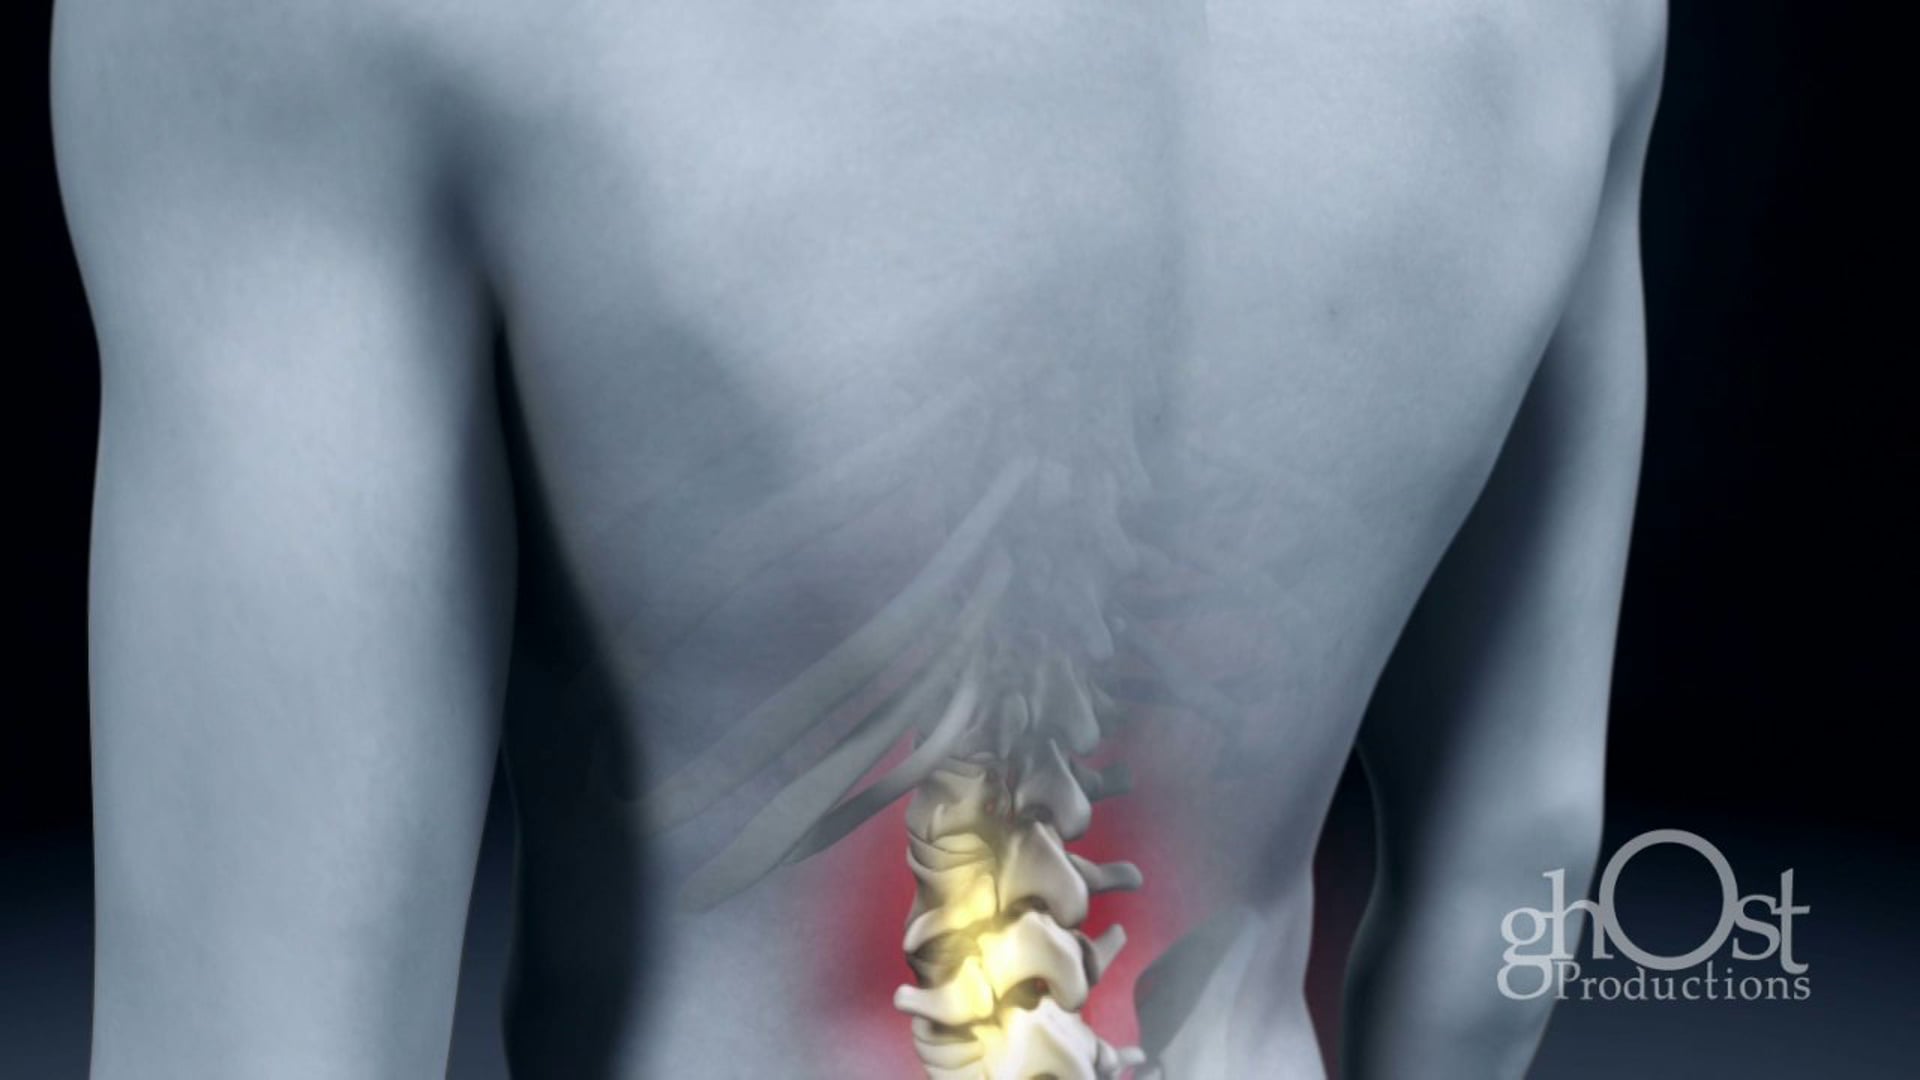

Ghost Medical, a division of Ghost Productions, has played a key role in helping Vionic Orthaheel achieve their goals. Through the use of advanced medical animation and visualization techniques, Ghost Medical has helped Vionic Orthaheel to showcase the benefits of their products and educate healthcare professionals and patients about the importance of foot health.